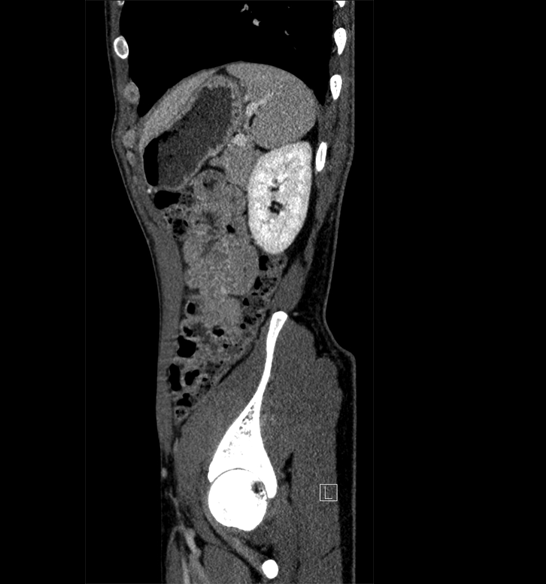

Body

Covers abdominal CT anatomy.